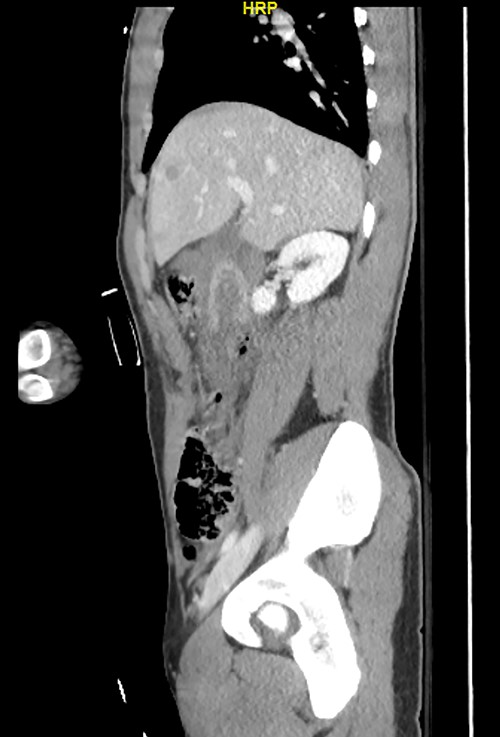

Postoperatively, the ND and retrograde duodenostomy tubes were maintained on continuous suction. Feeding through jejunostomy tube was initiated on postoperative Day 2, and the ND tube was removed on postoperative Day 23 when oral feeding was initiated. Although postoperative CT and Gastrografin swallow confirmed good anastomosis without evidence of leaks (Figs 4–7), The prolonged hospital stay and the delays in removing ND tube and initiation of the oral intake was because of persistent sepsis and high WBC counts, which was later confirmed to be secondary to abscess in his right thigh.